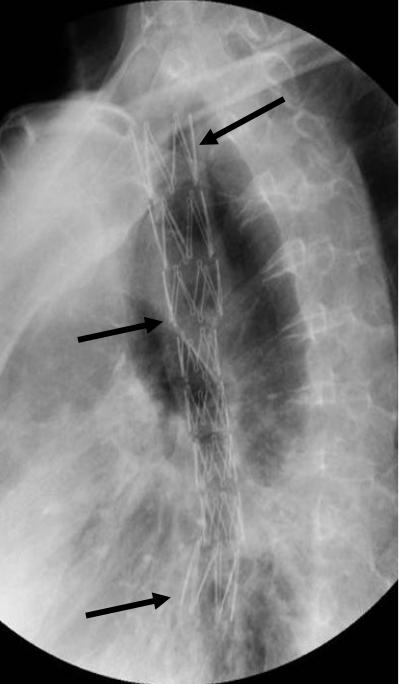

故事中的梁伯,后来请了介入科医生会诊。介入医生征得梁伯及其家人同意后,在电视透视引导下,顺利地植入了食管带膜支架。所谓带膜支架,也称“覆膜支架”,是在金属支架上覆盖了一层或双层的高分子耐腐蚀薄膜,可以起到腔内隔绝作用。食管带膜支架的植入起到了“一石二鸟”的作用,即支架的支撑恢复了食管通畅,支架的覆膜又成功地封闭了食管气管瘘——吃饭的问题很快就解决了!有了饮食调理,梁伯的身体状况逐渐好转。再次出现在老友面前,达观的梁伯说道:不听老友言,吃亏在眼前;不过好在做了介入,至少不会成为“饿死鬼”了!

食道内已经植入支架